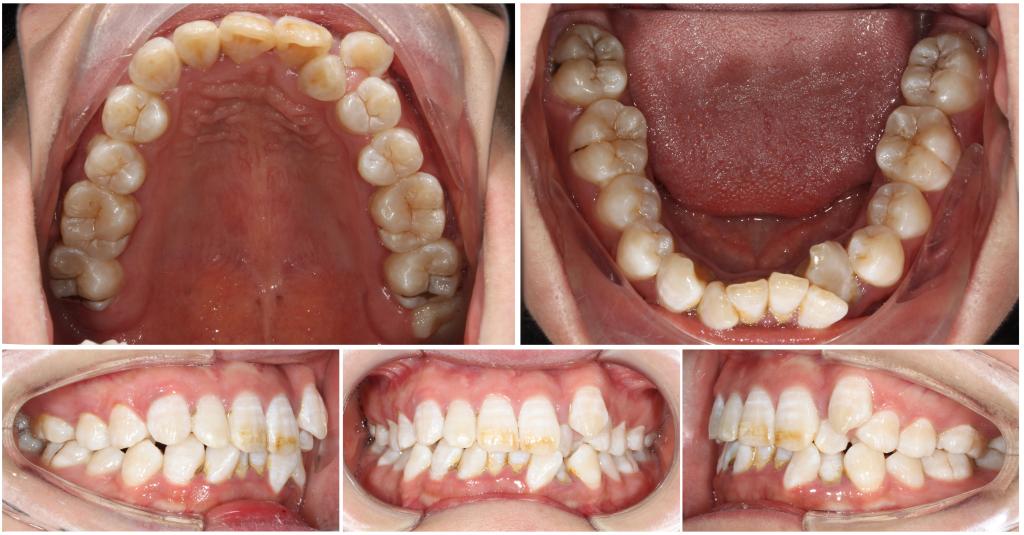

2. 口内像及面部相片:用照片的形式直观记录矫治前、中、后各个阶段面部及牙状态是正畸检查诊断的重要一环。